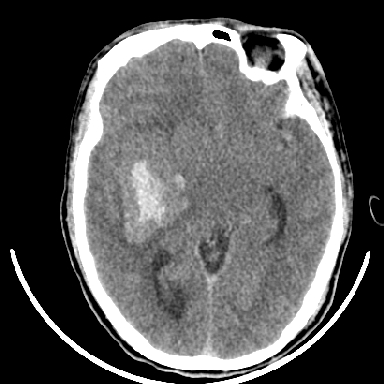

考虑高血压性脑出血,依据:

1是高血压性脑出血的好发部位,形态呈肾形,是高血压性脑出血的常见形状

2增强时占位效应加重了,考虑出血还没有停止

3病灶周围水肿不是太厉害,一般肿瘤出血水肿多非常明显

4病灶周围的‘软组织’影没有明显的强化

5至于脑血管畸形引起的出血,暂时没有看到明显的畸形血管影,也不太支持

支持右侧基底节脑出血

右侧基底节区脑出血.

支持右侧基底节区(主要为外囊区)原发性脑出血。

另附部分资料:“血液溢出血管外形成血肿,其内含有大量血红蛋白、血浆白蛋白,球蛋白,因这些蛋白对x线的吸收系数高于脑质,故ct呈现高密度阴影,ct值达40~90h,最初高密度灶呈非均匀一致性,中心密度更高,新鲜出血灶边缘不清。基底节区血肿多为“肾”型,内侧凹陷,外侧膨隆,因外侧裂阻力较小,故向外凸,其它部位血肿多呈尖圆形或不规则形”

术中抽出40ml陈旧血液,血肿底部似见一条索血管影